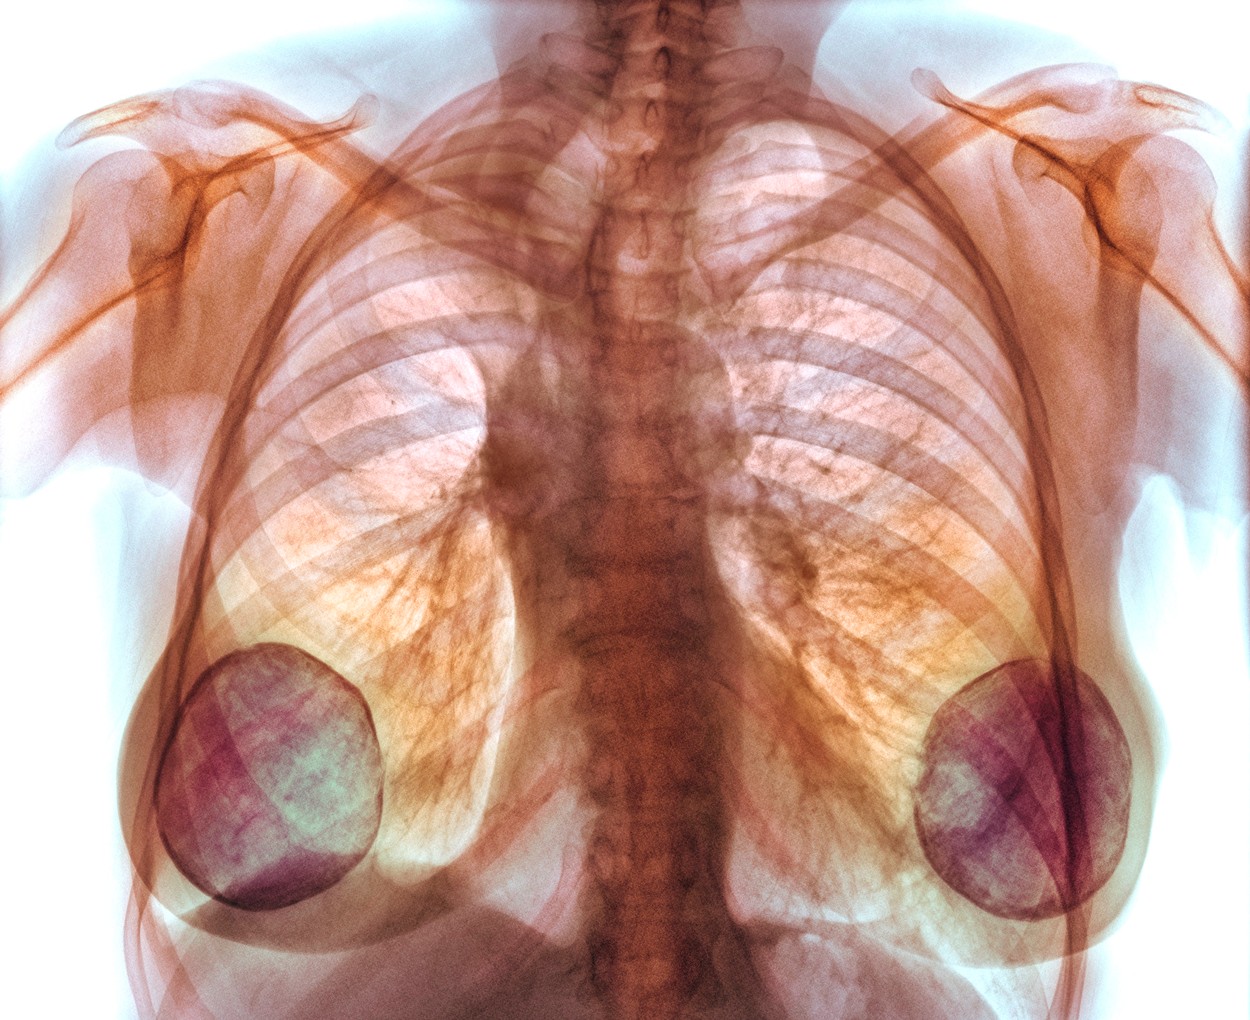

Sâni măriți cu silicon industrial. Mii de femei vor primi despăgubiri. Medic chirurg: „Implantul era pur şi simplu descompus”

- 2.700 de femei care au primit implanturi mamare defecte ar putea fi despăgubite.

- Compania a utilizat silicon industrial pentru umplerea unor implanturi mamare.

2.700 de femei care au primit implanturi mamare defecte şi care au suferit din cauza asta ar putea fi despăgubite.

Asta a stabilit Curtea de Apel din Paris, în urma unui proces care a durat 10 ani. Asociaţia pentru Inspecţie Tehnică Germană a fost condamnată după ce a certificat implanturile companiei franceze Poly Implant Prothèse, care a utilizat un material ieftin şi neaprobat pentru uz uman. Asta a dus la probleme grave de sănătate: uneori chiar şi cancer în ultimul stadiu.

Vlad Pieptu, medic chirurg: „Chiar dacă nu erau simptome implantul era pur şi simplu descompus complet şi în interiorul sânului era dezorganizat acel gel siliconic a fost un producător bun care în căutarea unui mod de a scădea semnificativ costurile şi a creşte într-un mod mişelesc profiturile au schimbat reţeta unui produs”

Avocatul victimelor spune că a fost un proces dificil şi că această decizie a adus sfârşitul unei îndelungate perioade de îndoială. Cu toate astea, nu se ştie încă valoarea despăgubirilor. Printre femeile despăgubite se numără şi 7 românce, din totalul de 250 de femei de la noi din ţară care au avut implanturi de la acea companie.